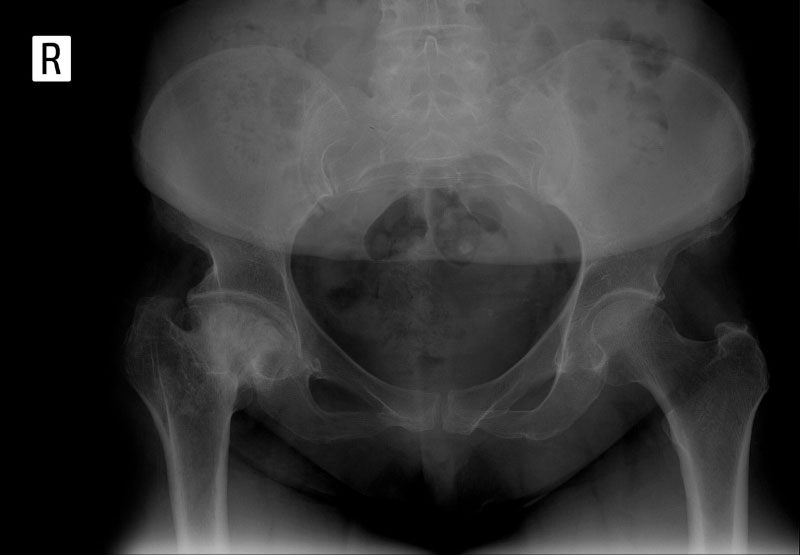

Một số hình ảnh viêm khớp háng trên Xquang qua từng giai đoạn

Bác sĩ có thể dùng thang điểm Kellgren và Lawrence để đánh giá tình trạng viêm khớp háng trên X-quang. Hệ thống này phân biệt cấp độ tổn thương từ nhẹ đến nặng, dựa trên những đặc điểm cụ thể được phát hiện. (1)

Cấp độ thoái hóa khớp qua từng giai đoạn, đặc điểm trên X-quang:

Cấp độ 1 – Nghi ngờ: Khe khớp có dấu hiệu hẹp nhẹ, có thể xuất hiện gai xương nhỏ quanh đầu khớp.

X- quang cho thấy khe khớp hẹp nhẹ ở cả hai bên, xơ cứng xuất hiện dưới sụn tại ổ cối.X-quang AP và Lauenstein bên thể hiện khoảng cách khe khớp, xuất hiện gai xương – Ảnh: Tạp chí điện tử SpringerLink Nature, Hoa Kỳ.

Cấp độ 2 – Nhẹ: Khe khớp hẹp rõ hơn, gai xương dần rõ ràng, xơ cứng tại xương dưới lớp sụn.

X-quang cả hai khớp háng cho thấy khe khớp hẹp nhẹ ở mặt trên bên của ổ cối kèm theo xơ cứng dưới sụn.Hình ảnh X-quang của nam giới 58 tuổi bị viêm khớp háng phải nghiêm trọng, cổ xương đùi dày lên, khe khớp hẹp rõ.